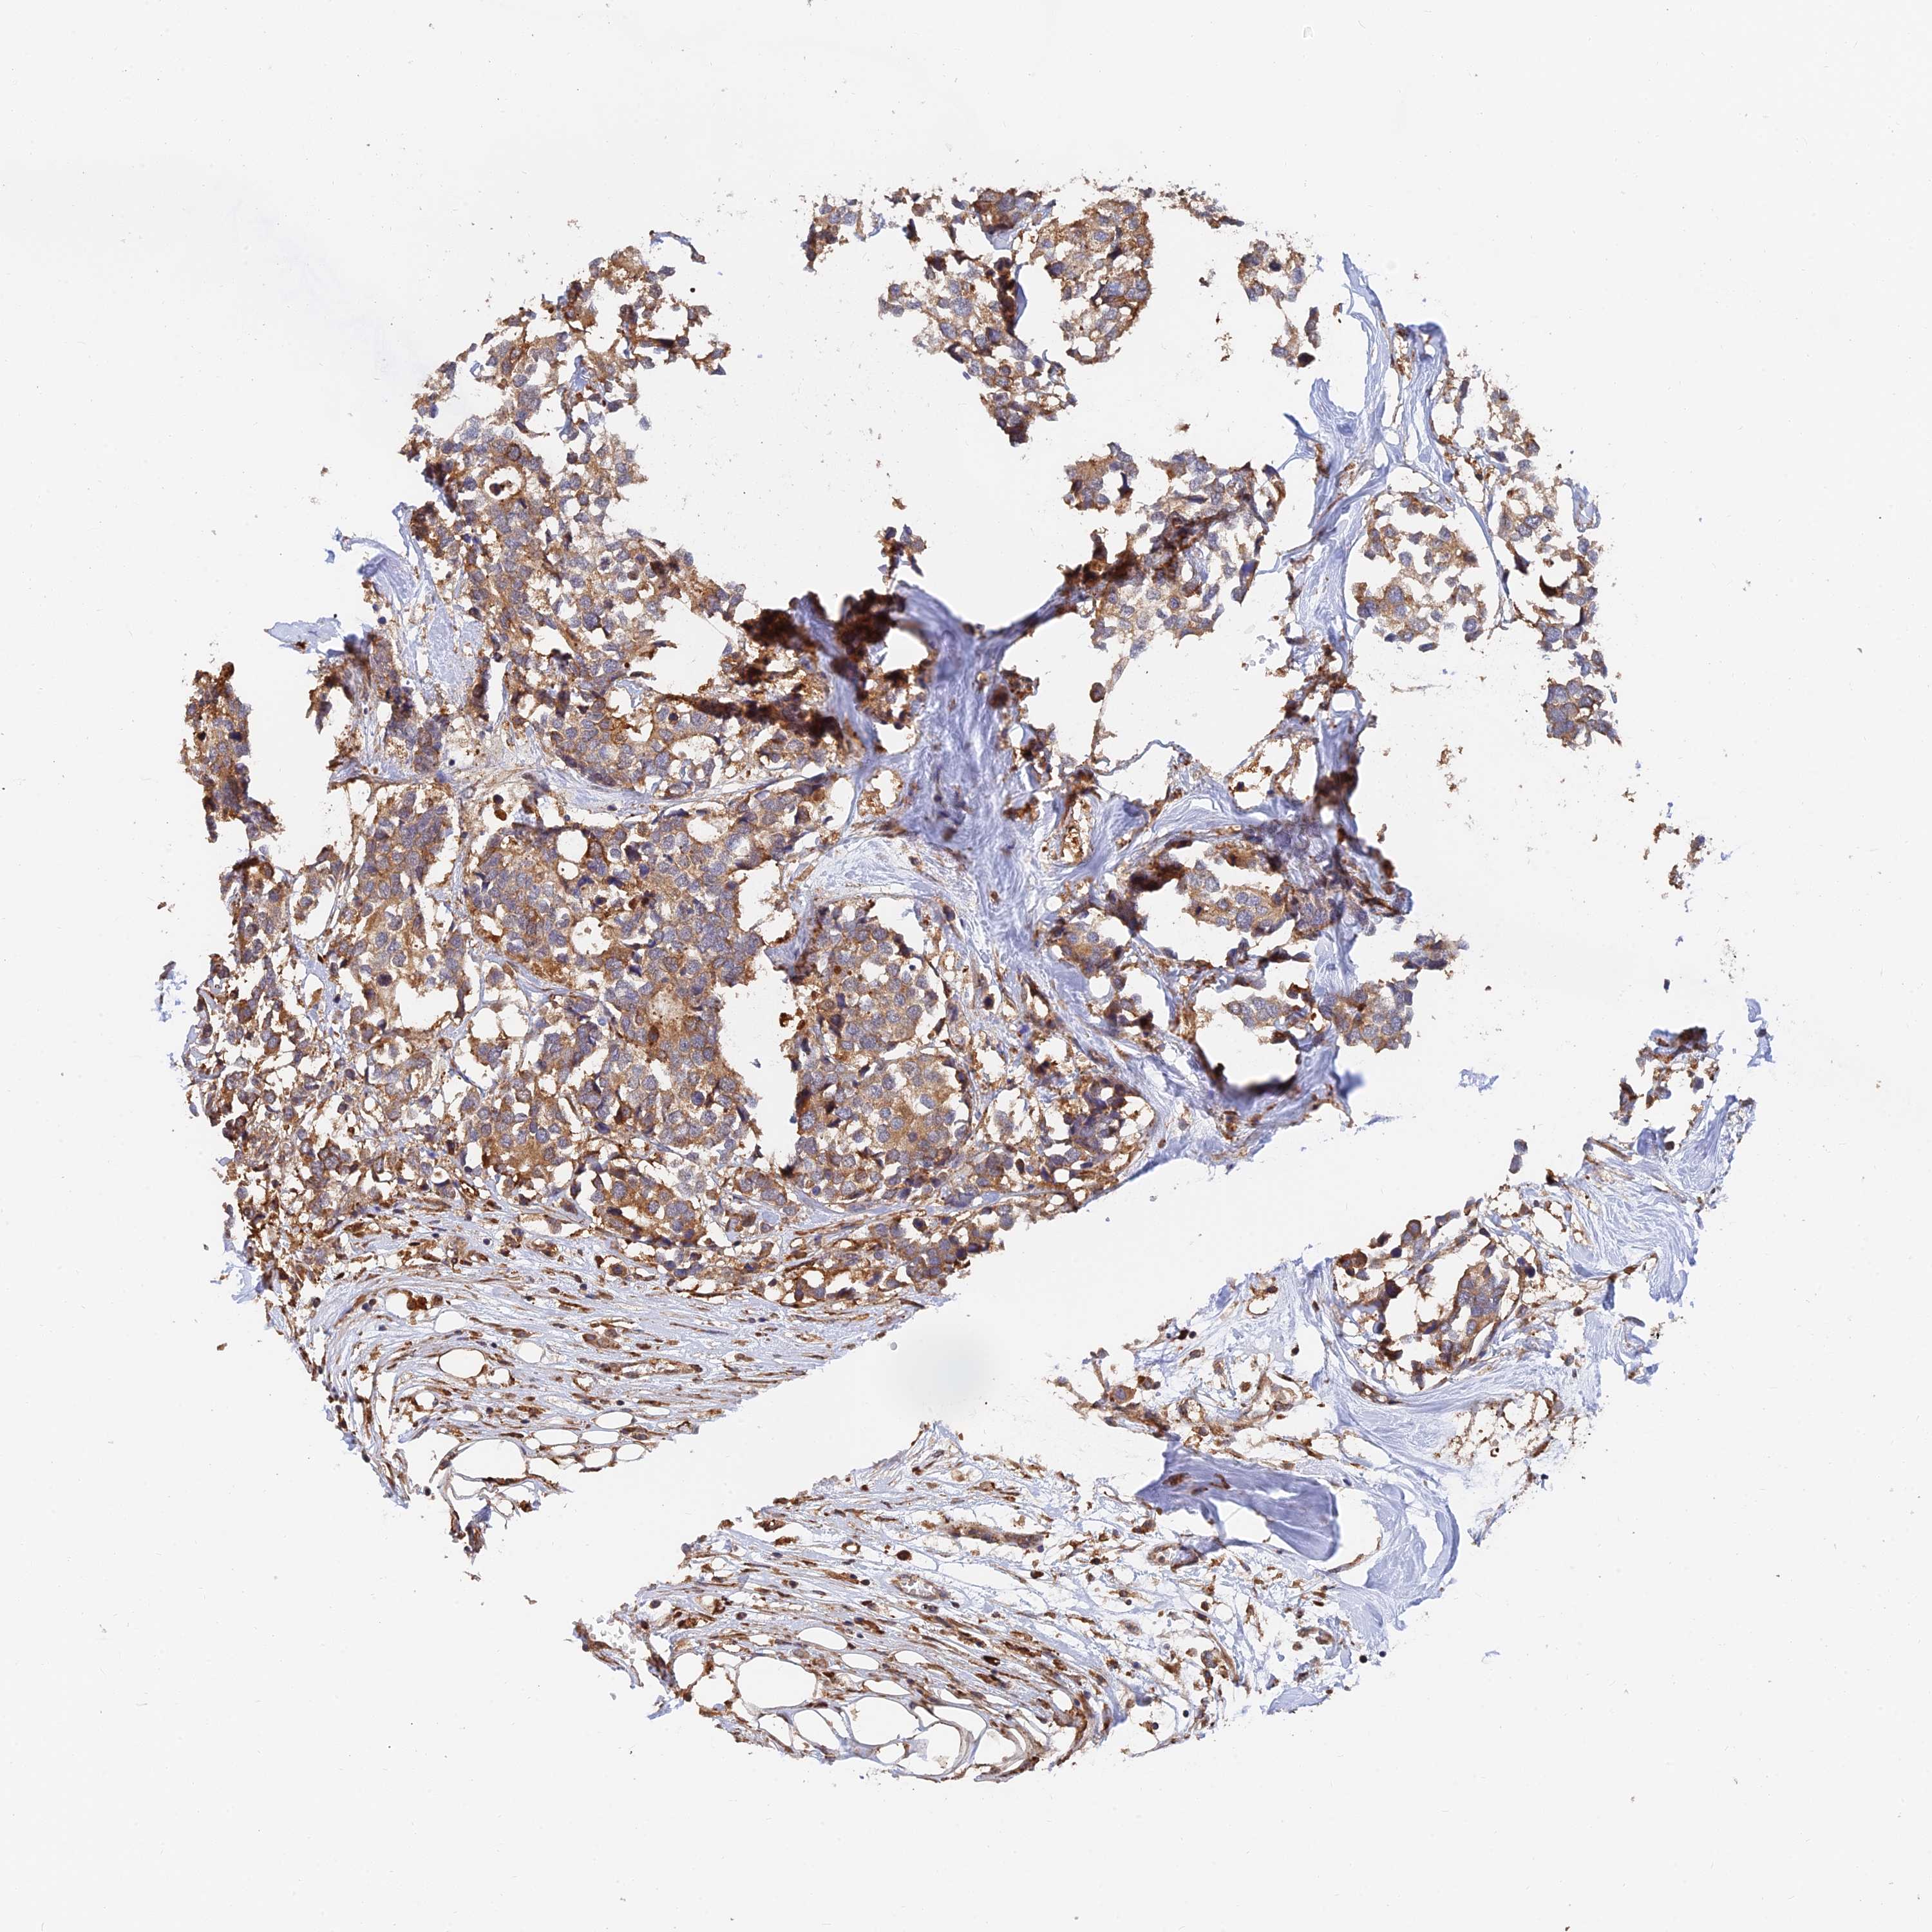

CANCER BREAST CANCER Show tissue menu

BRCA TCGA BRCA VALIDATION PROTEIN EXPRESSION